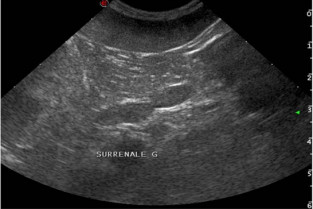

Echographie des surrénales : aspect normal et lésionnel

Cours

Julien Fritz

Guillaume Gory

Aspect pathologique des glandes surrénales